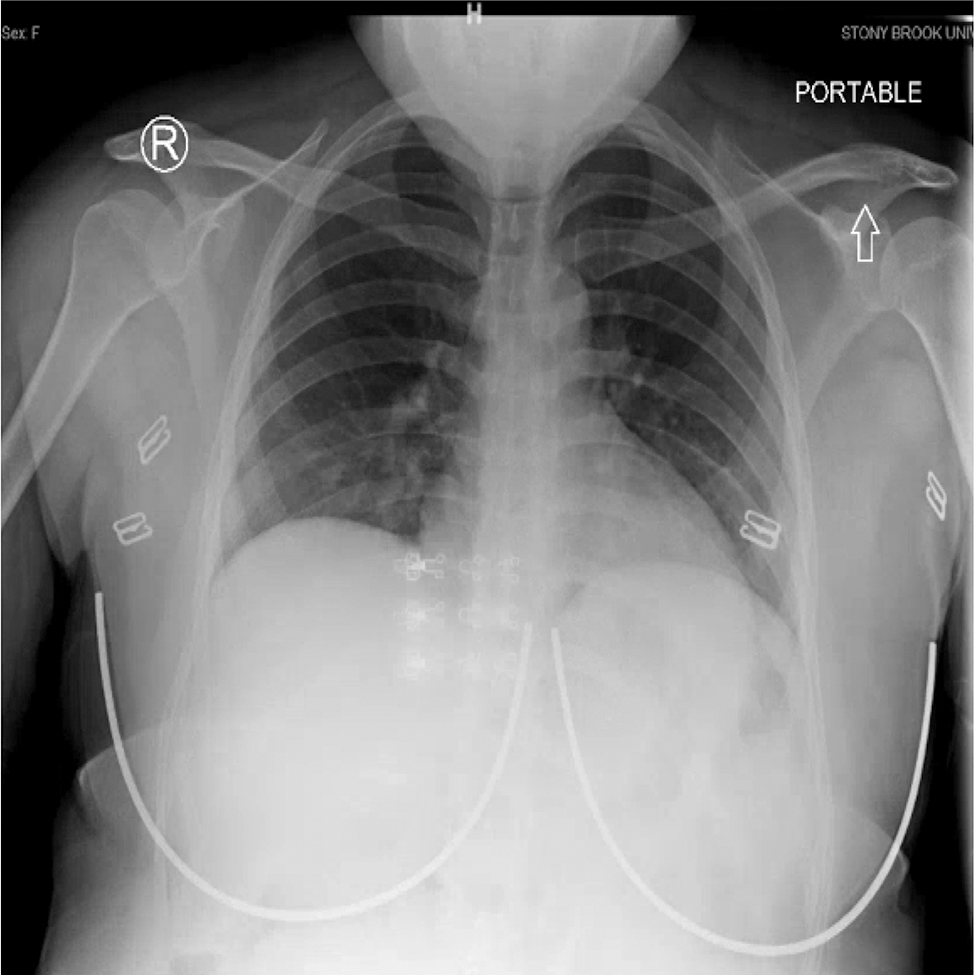

In the emergency department her maximum temperature was 39.4 °C, heart rate ranged from 110 to 130 beats per minute, respiratory rate was 16 breaths per minute, blood pressure was 100/59 mm Hg, oxygen saturation was 99% on room air. Physical exam revealed an ill but not toxic appearing patient. Lungs were clear to bilateral auscultation, no increased work of respiration. Heart rate was tachycardic, but regular rhythm. Abdomen was gravid, non-tender, without suprapubic tenderness. There was no flank tenderness or costovertebral angle tenderness. Bedside ultrasound revealed a fetus in breech presentation, with posterior placenta and amniotic fluid index of 16. Initial chest X-ray was found to have no acute cardiopulmonary findings (Figure 1).

Chest X-ray on initial presentation for first admission. Radiologic impression: no acute cardiopulmonary process.